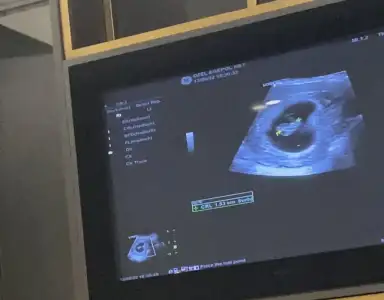

Genelde kalp atımı zamanındaki kere bakıyorlardı. 7 8 hafta civariCok heyecanliiii :)

Benimki ilk gittigimde fasulyemsiydi ama simdi bi ucgene benziyor sivri koseli degil tabi :)

Acaba bu kese sekli degisecek ki daha? Hangisini baz alicaz :)